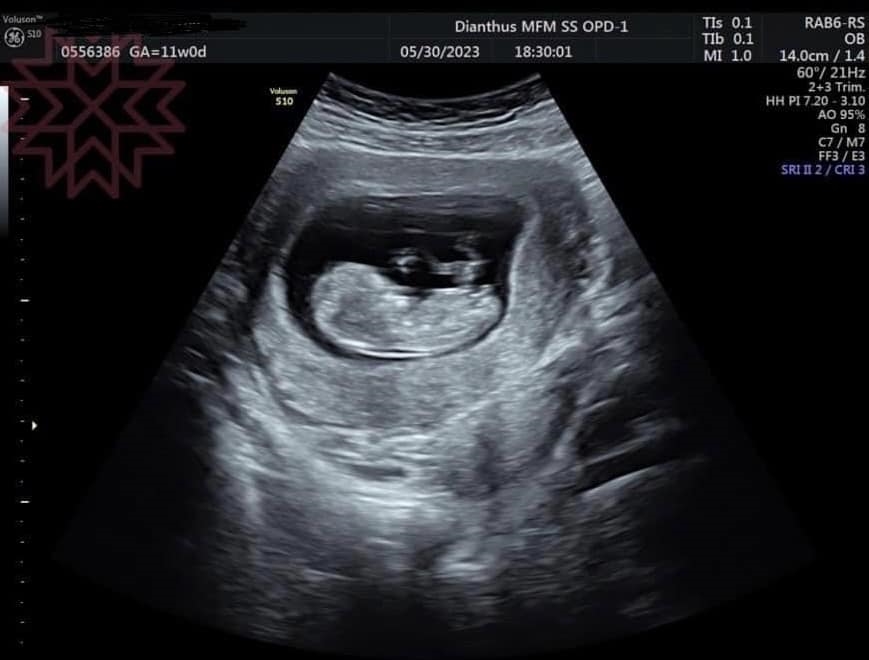

楊繡惠昨日突然在臉書發文,她還開心地說,「哈哈恭喜我吧!滿3個月再公開」。她也曝光了2張超音波照片,看起來似乎是寶寶的超音波照,讓大批網友都相當驚喜,懷疑是不是楊繡惠懷孕了,不少人也在底下留言恭喜,「恭喜姐啊」、「阿姊…恭喜…我雖然覺得怪怪的…但我沒證據」、「恭喜,期待~」。

後續有眼尖網友揪出1細節,發現這2張超音波的左上角有標示出孕媽咪的資訊,似乎是1名1992年出生的柯姓女子懷孕,「左上方有準媽媽的名字!」、「名字露餡了」、「左上角名字不是你的餒」、「超音波照片有媽媽的名字啦!媽媽應該是1992年的」。後來楊繡惠也將孕婦的資訊打馬賽克,但還是沒有說明超音波照片的真相為何。